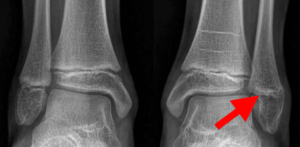

In children and adolescents, ankle fractures typically affect the tibia or fibula, often involving the growth plates—specialized areas of cartilage near the ends of long bones. Growth plates play a critical role in bone development, gradually hardening into solid bone as the child matures. However, because these growth plates are the last parts of the bones to solidify, they are particularly prone to injury and fractures. As adolescents approach the end of their growth phase, growth plates begin to close and harden, making them susceptible to transitional fractures during this maturing stage. Two common types of transitional ankle fractures are triplane fractures and Tillaux fractures, which require specific treatment approaches depending on their severity and location (refer to the Treatment section for more details)